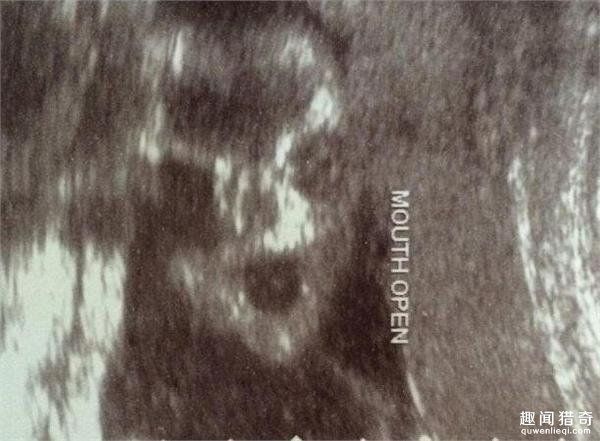

其中还有一张b超图,上面是一个小小的胎儿

14周男宝b超下的样子,很真实,怀孕的宝妈看过来!